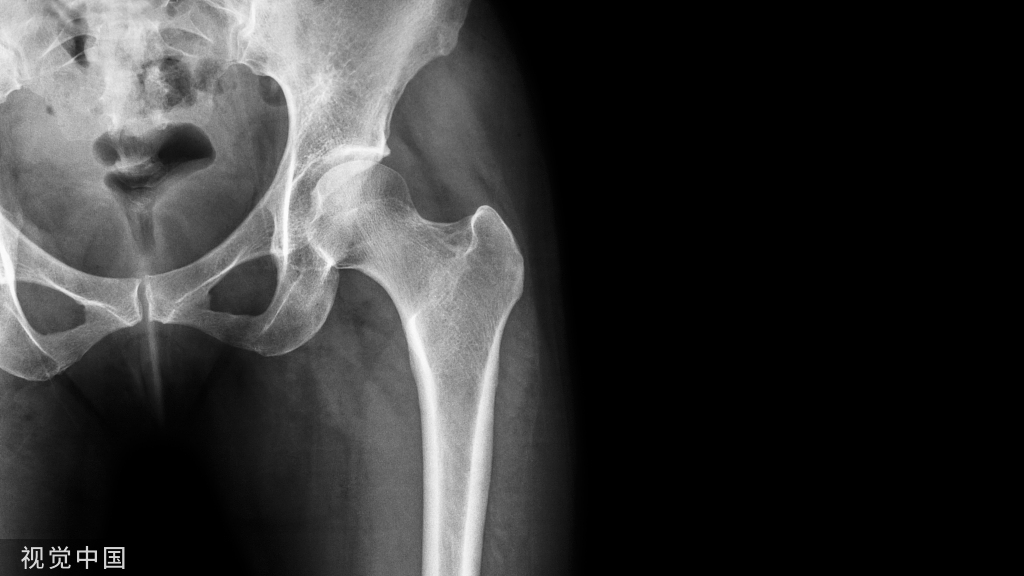

髋关节病变:

• 5% 出现孤立的膝关节症状,尤其是在较年轻的人群中

• 股骨头骨骺滑脱

• Legg-Calves-Perthes 病

髋部骨折、股骨干骨折(应力性骨折)